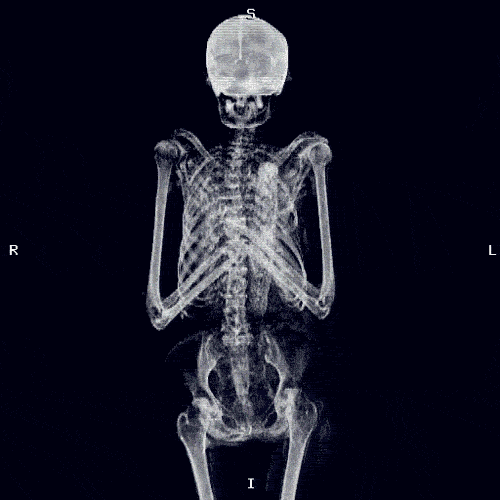

TDN > Actualité Le corps humain aux rayons X … en GIFs animés ! Publié par Elsa Fanjul le 11 Jan 2014 à 10:08 Suivez nous sur Google News Partagez cet article En bonus, découvrez le Giphoscope, ou comment faire des GIFs dans la vraie vie ! Veuillez laisser ce champ videRejoignez nos 875 726 abonnés en recevant notre newsletter gratuite N'oubliez pas de cliquer sur l'email de validation pour confirmer votre adresse email. Si vous ne l'avez pas recu vérifiez dans vos spams. Dernière étape pour confirmer votre inscription : il faut cliquer l'email de confirmation. Vérifiez dans vos spams si vous ne l'avez pas reçu ! A bientôt ! Page précédente Laissez un commentaire Votre adresse e-mail ne sera pas publiée. Les champs obligatoires sont indiqués avec * Votre commentaire * Votre pseudo * Votre adresse e-mail * Cliquez ici pour commenter